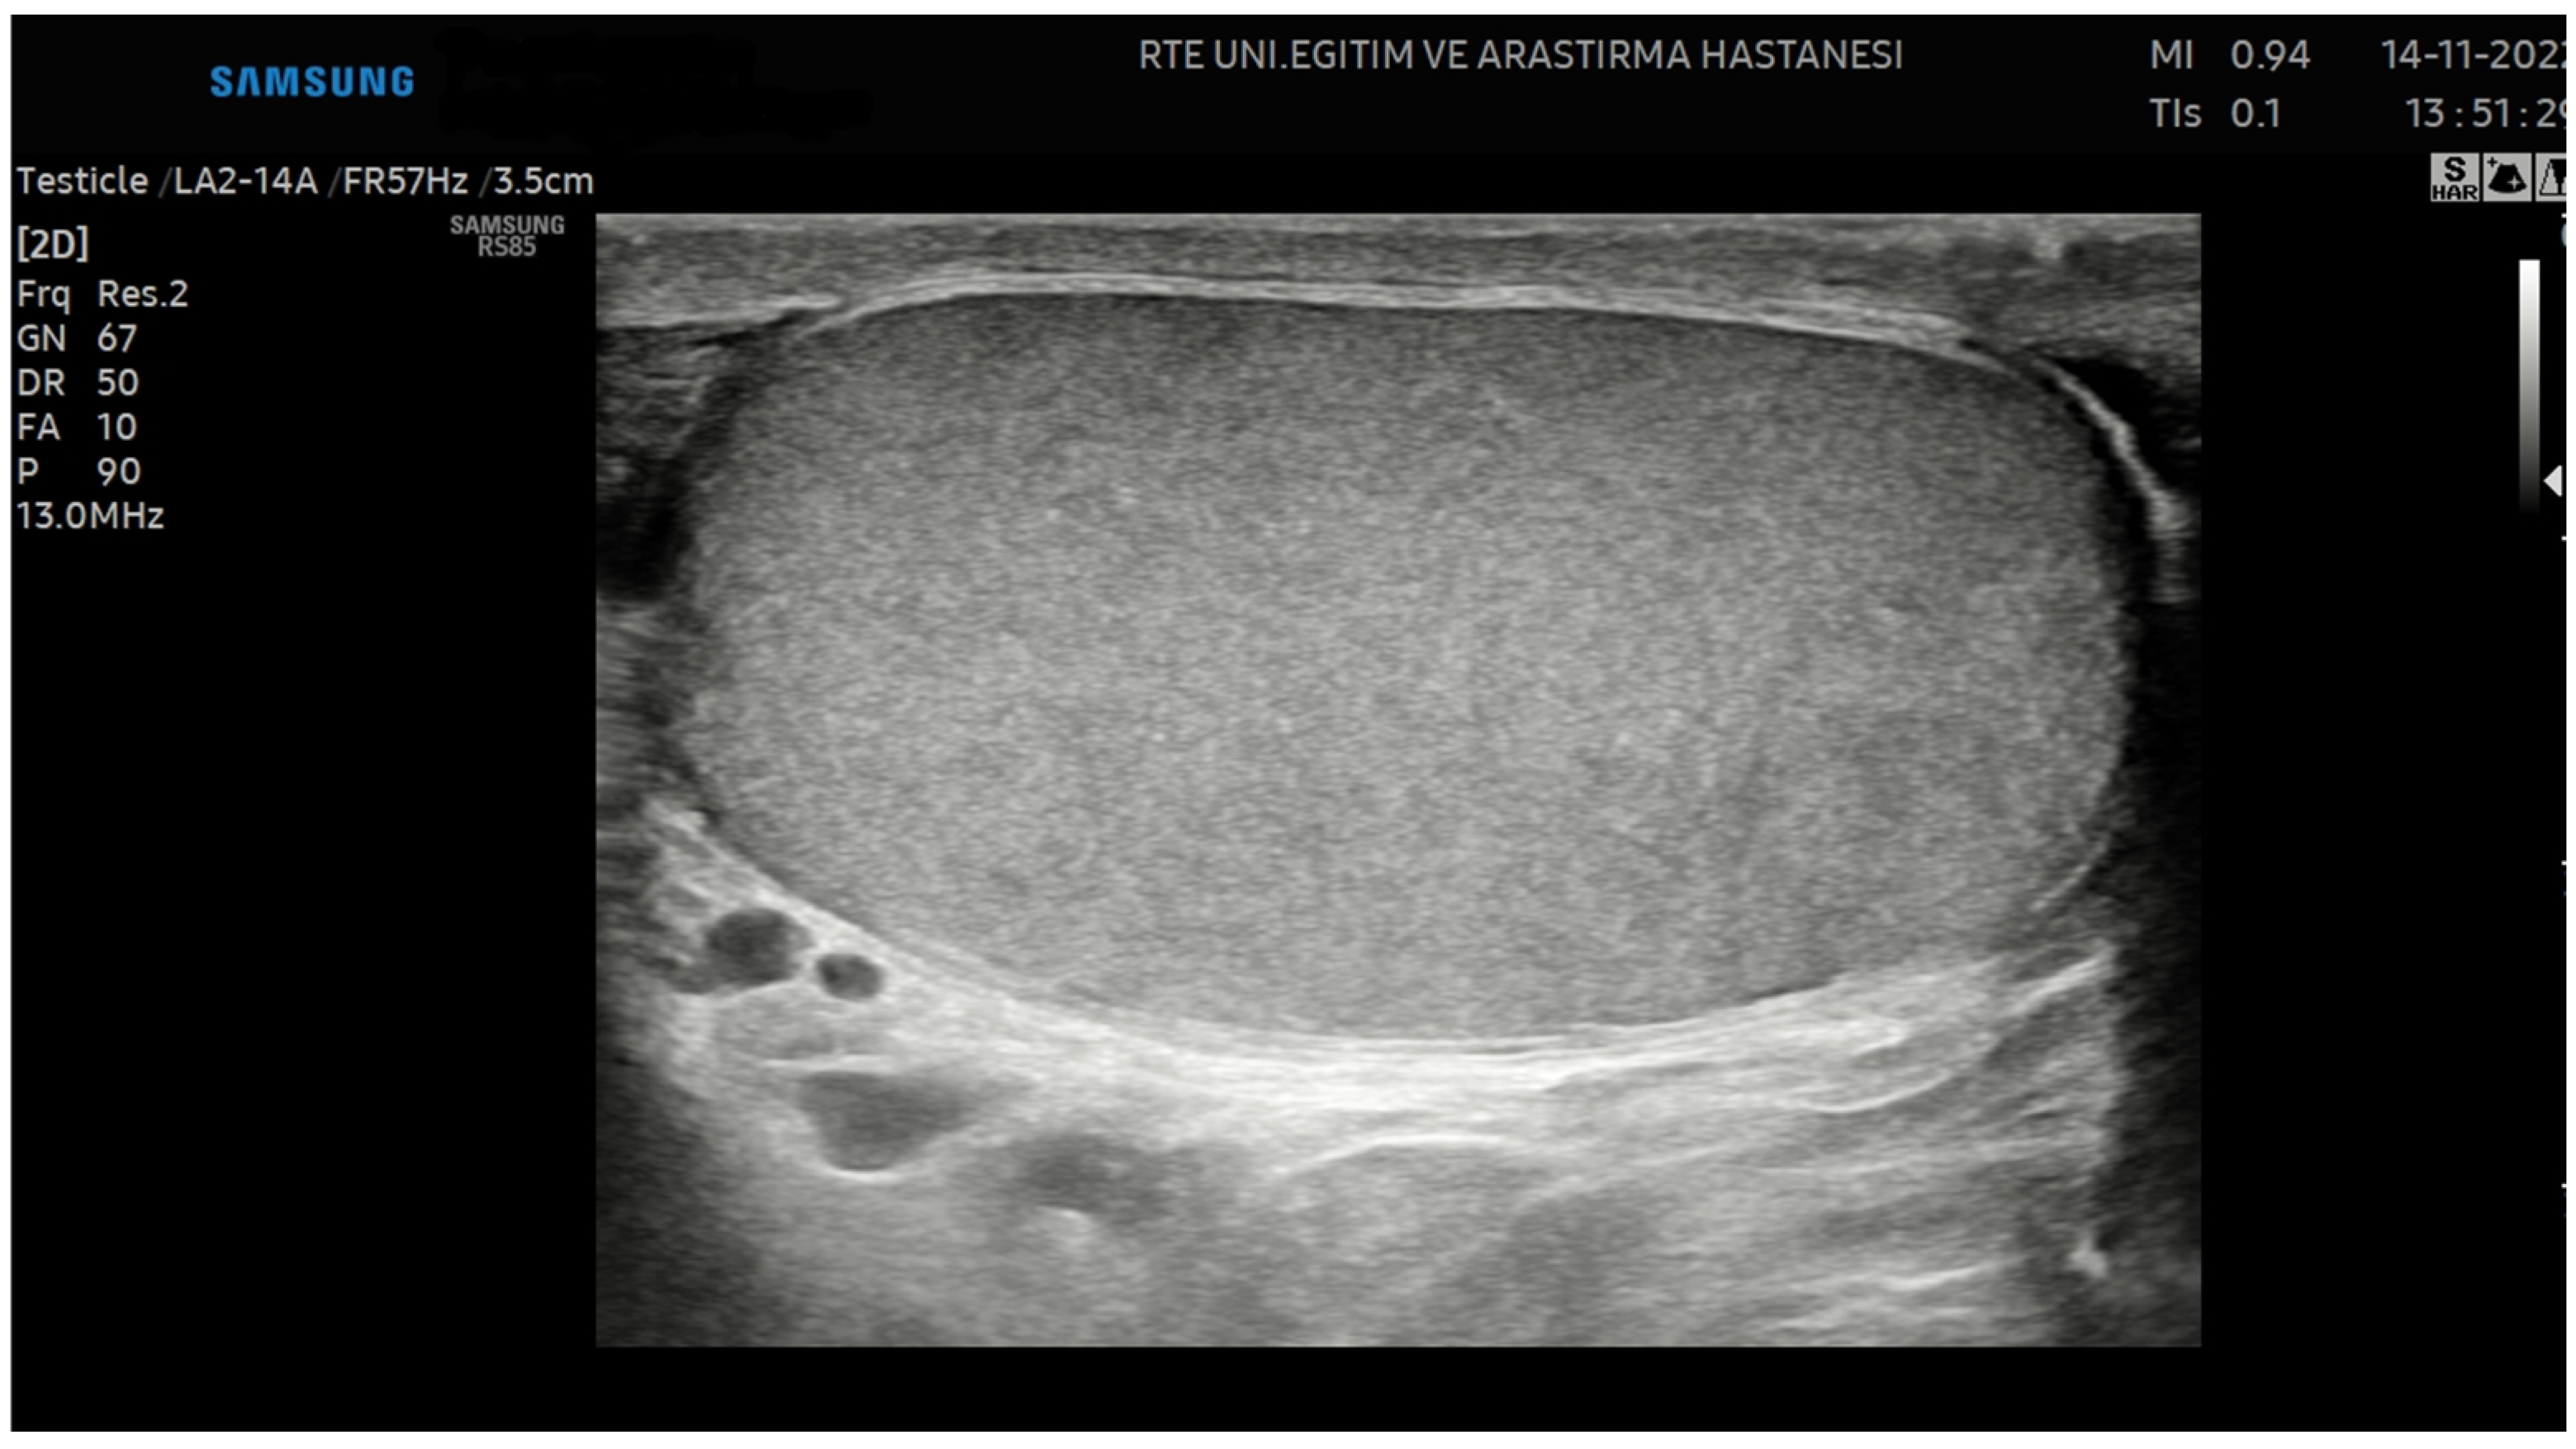

Ultrasonography examinations for all patients in this study were performed by a single radiologist using the Samsung RS85 Prestige Ultrasonography device with the LA2-14A linear probe. The testicular preset, THI mode, and 13.0 MHz parameters were standardized for all patients. To ensure consistency and avoid altering grayscale values, the Tissue Gain Compensation (TGC) was kept constant, and the gain settings were not modified for any patient.

Following semen sample collection, all the patients underwent ultrasonography on the same day. Each patient was examined in the supine position, with the penis positioned in the suprapubic region. Initially, grayscale ultrasonography was used to assess the location, contours, echogenicity, and dimensions of both testes.

The short and long axes of the testes were measured, and the testicular volumes were calculated using the following ellipsoid formula: [length (cm) × width (cm) × depth (cm) × 0.71] [9]. However, this ellipsoid formula may not fully account for natural irregularities or asymmetries in testicular shape. Variability in the precision of the measurements and differences in testicular morphology may lead to inaccuracies in volume estimation. In addition, conditions such as testicular atrophy, hydrocele, or the presence of tumors can cause significant deviations from the idealized ellipsoid shape, further limiting the accuracy of the formula [21]. Images were captured along the longitudinal axis of the testis, ensuring that the mediastinum testis was excluded and that the entire testicular contour was encompassed (Figure 1).

Figure 1.

Image of the testis captured along the longitudinal axis.